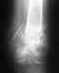

последвия перелома снимки прилогаются ,ваше мнение?

здравствуйте! у меня есть пару вопросов, я сломал ключицу 1й раз со смещением , меня не стали ложить в больницу , сделали колечки ( повязку ) и отправили домой после чего я обследовался у районного травматолога. Ходил навсякие процедуры,контрольные снимки, сменили повязку на болле удобную,и после закрытия справки через 5ть недели сломал заново тоесть в общей сложности я отходил 6 недель как положено с повязкой и на 11й недели сломал заново. На этот раз меня положили в больницу, таже ситуация была с небольшим смещением, на счет операции ничего не говорили,после выписки, я опять же наблюдался у травматолога на процедуры не ходил так как сессия не позволяла. сейчас я уже закрыл 2ю спраку даты переломов такие 9 сентября и 24 ноября,дискомфорта никакого не ощущаю рука полностью функционирует,а вот как поведет себя при тяжелых нагрузках незнаю. Соответствено такие вопросы :1) за какое сростается ключица?2)через какое время и какие нагрузки можно на нее оказывать?(качалка) 3)можно ли было делать операцию? за счет государства или же за мой? 4)какие лекарства посоветуете пить чтоб были крепкие кости?или для профилактики вот снимки

• Кликните для загрузки файла 28112007(001)1.JPG